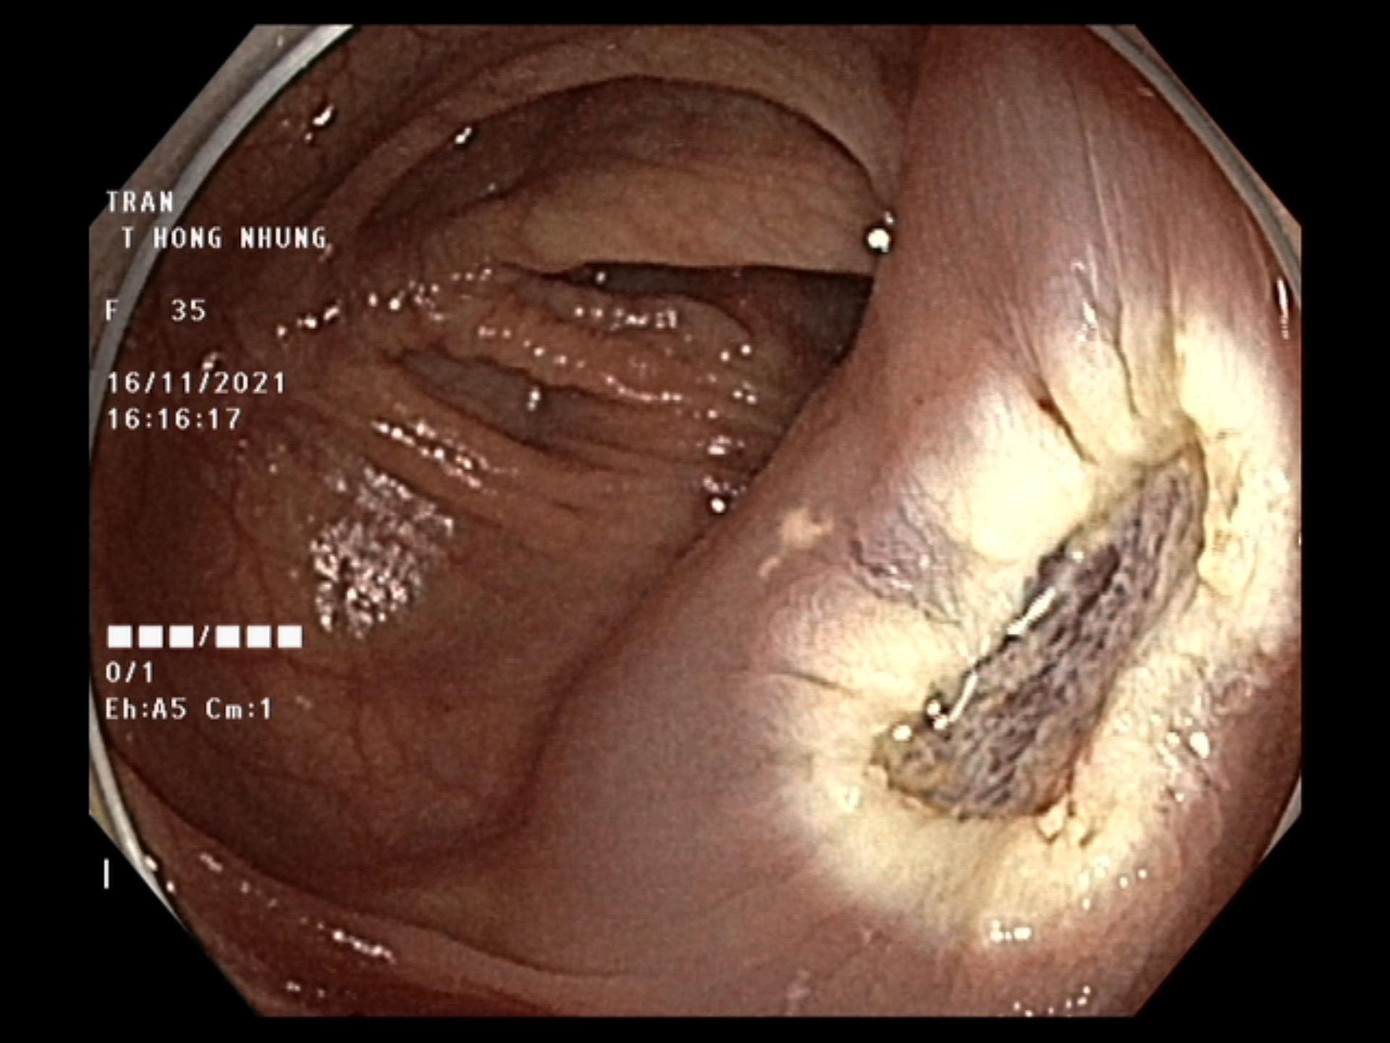

Cuối tháng 10 vừa qua, chị T.T.H. Nhung (35 tuổi) trú tại Hoàng Mai, Hà Nội đi kiểm tra sức khỏe định kỳ kết hợp nội soi dạ dày và đại tràng. Trong quá trình nội soi đại tràng, các bác sĩ phát hiện một khối polyp kích thước 3,5cm tại đại tràng ngang. Theo đánh giá, đây là một khối polyp có kích thước lớn, chân rộng. Những polyp có tính chất này thường chứa nhiều mạch máu nuôi dưỡng và có nguy cơ ung thư cao.

| Hình ảnh nội soi đại tràng của bệnh nhân T.T.H. Nhung |